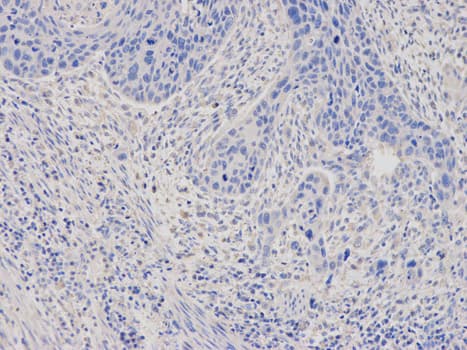

Anti-Ferritin Light Chain antibody(AB186871)

Rabbit Polyclonal Ferritin Light Chain antibody. Suitable for WB, IHC-P and reacts with Human samples. Cited in 1 publication. Immunogen corresponding to Recombinant Full Length Protein corresponding to Human FTL.

Applications IHC-P, WB